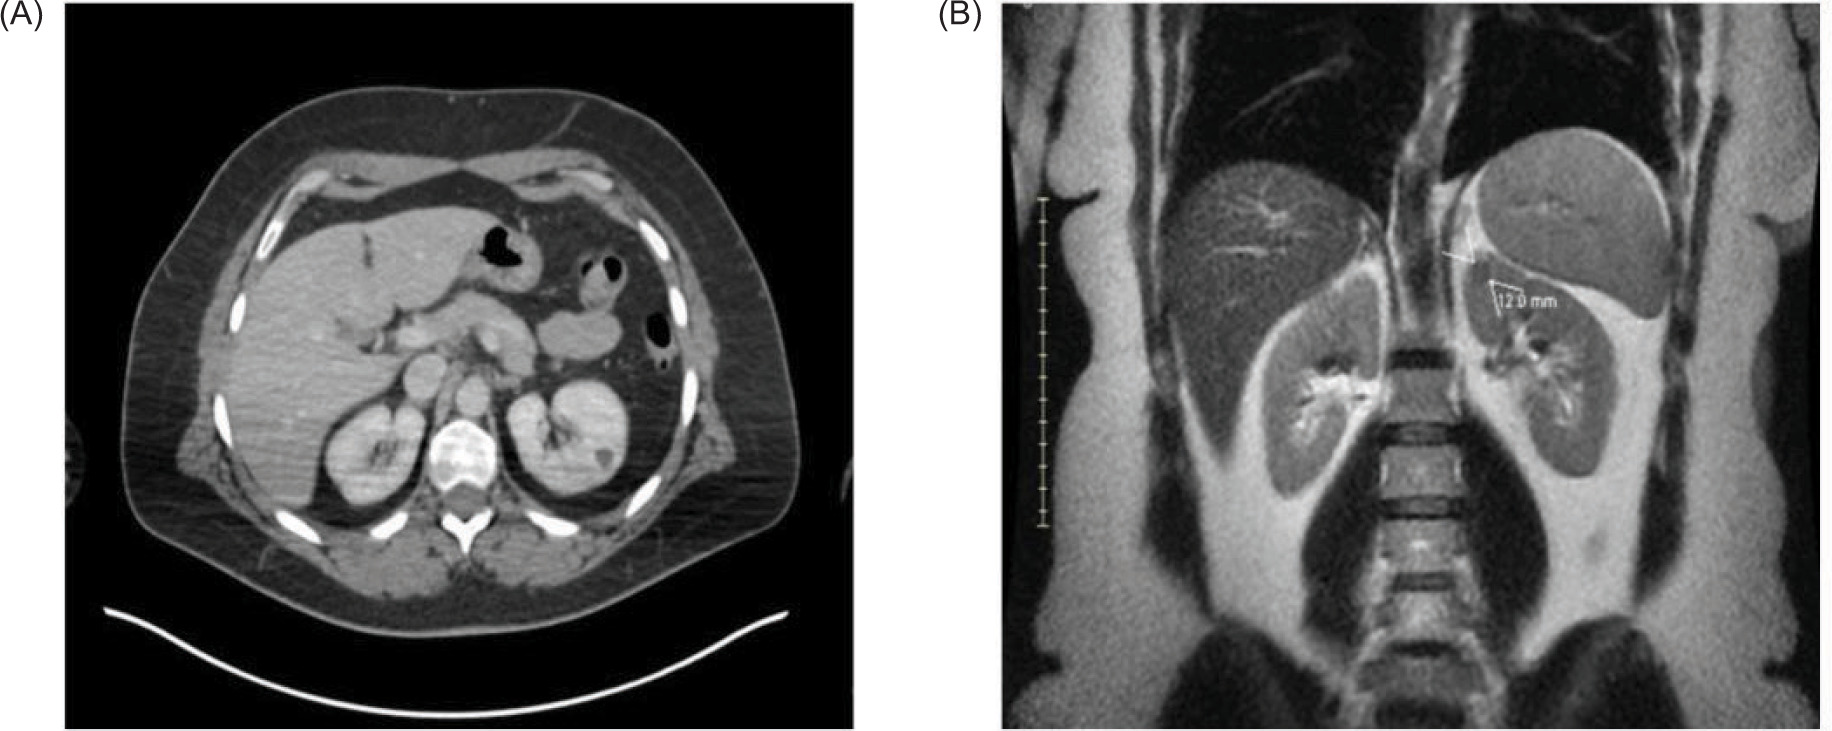

Figure 1: Small renal mass in the upper pole of the left kidney as seen on CT and MRI. (A) Axial view from CT demonstrates a 12 mm lesion. (B) Coronal view from the abdominal MRI also shows a solitary 12 mm upper pole anterior endophytic lesion of the left kidney. Pathology indicates metastatic ocular melanoma.

The patient was initially diagnosed with a tumor of the choroid of the right eye, identified pathologically by immunohistochemistry as malignant melanoma. MRI of the abdomen at the time of diagnosis showed the liver, kidneys, and adrenals were within normal limits. The patient was treated with plaque brachytherapy, 21 seeds and an 18 mm plaque left in for 4 days. The patient remained in remission for 9 years until the detection of a 1.5 cm soft tissue nodule in the anterior upper pole of the left kidney on routine surveillance imaging. The patient presented with no symptoms, no hematuria, flank pain, or weight loss. Whole body PET-CT scan showed no other suspicious lesions, and physical exam revealed no cutaneous lesions. Recurrence of melanoma to the left kidney was confirmed, and renal cell carcinoma (RCC) was ruled out by percutaneous renal mass biopsy (Figure 1). After consultation with urology and surgical departments, and medical oncology, the decision was made to pursue surgical removal of this solitary melanoma metastasis. The tumor was of low complexity, with a RENAL score of 6 (R1 E3 N1 L1), for which AUA guidelines indicate PN to be appropriate (19). The patient underwent robotic partial nephrectomy with final pathology confirming melanoma with immunochemistry positive for SOX-10 (20). PN had the same level of difficulty as a nonmelanoma renal mass of similar size. The operative time was 2.5 h, and the length of hospital stay was 3 days. To date, the patient has been monitored with serial imaging every 6 months. No adjuvant systemic therapy was given post-nephrectomy, as the patient had no other evidence of disease at that time, and systemic options for ocular melanoma are limited.